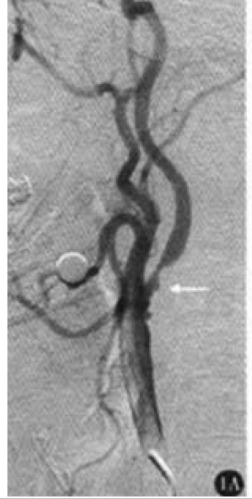

What's the Diagnosis?